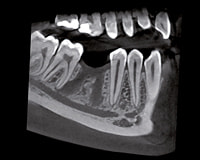

3D CT scan

直径8×高さ8㎝で160μmの高精細な画像を提供します。ORTHOPHOS XG 3Dは、たった1回のスキャンで全顎の撮影が可能で、一画面で広い診断領域を観察することができます。

日常診断の様々な診査・診断に使用することができます。

迅速な診断と低被ばくを同時に実現している装置です。